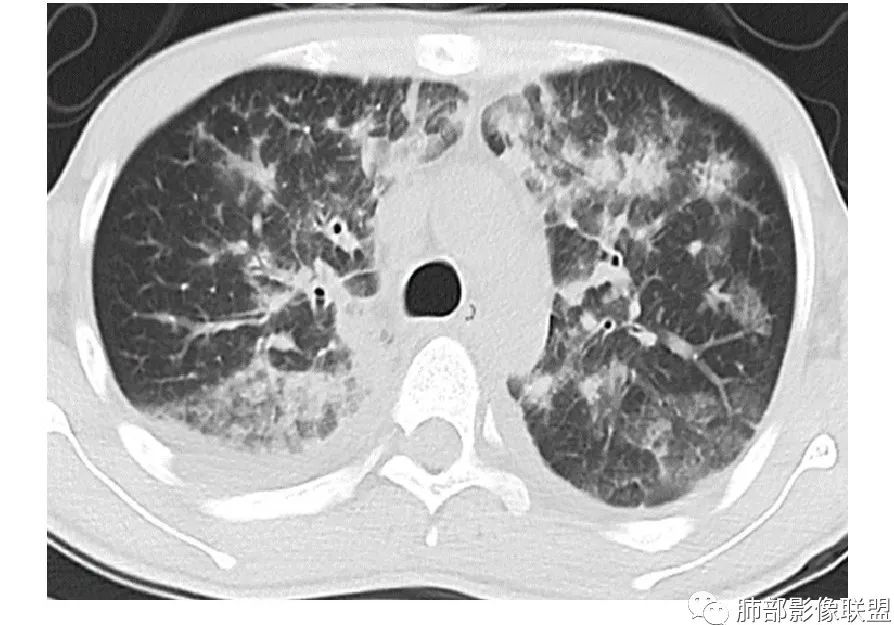

周一晚读病例:男性45岁,发热、纳差,全身散在暗紫色皮疹,结合CD4,符合HIV;肺部影像表现:两肺散在实性结节及磨玻璃密度影,实性结节伴晕征,部分沿支气管血管束分布,支气管血管束增粗,以两肺下叶为著,类似火焰征,双侧胸腔少量积液;首先考虑卡波西肉瘤,鉴别淋巴瘤增值性病变,淋巴瘤样肉芽肿/淋巴瘤,最后挂上马尔尼菲青霉菌病。

两肺弥漫性性结节状、小片状及片状带晕的病灶,煎蛋征、点晕征,主要分布两肺中下叶,病灶周围小叶间隔增厚呈网格状影,部分病灶累及胸膜,伴两侧胸膜增厚。

2.本例双肺小叶间隔增厚明显,多发结节影及片状实性密度影,沿血管支气管束分布为主,两侧较为对称,病灶多环以磨玻璃晕,边界不清。

双侧胸腔少量积液。双肺门及纵隔未见明确肿大淋巴结,纵隔结构间隙模糊。

3.有学者将这种具有沿双肺支气管束分布的实性密度片影描述为“火焰征”,认为具有一定特征性,单就影像表现而言,这种影像表现也可以见于其他病损或多种病理改变的叠加。

1.结节型:两肺沿支气管血管束分布的结节影,呈火焰状或星芒状、挂果征,局部周围出血磨玻璃影(肺泡出血或水肿)。

2.支气管血管束增粗型:

肺门周围支气管壁呈“套袖样”改变。

3.肺炎渗出型:

斑片渗出影,部分融合呈“火焰样”,同时有火焰样结节,小叶间隔增厚等表现。

还可以有纵隔及腋下淋巴结增大,胸腔积液等表现。